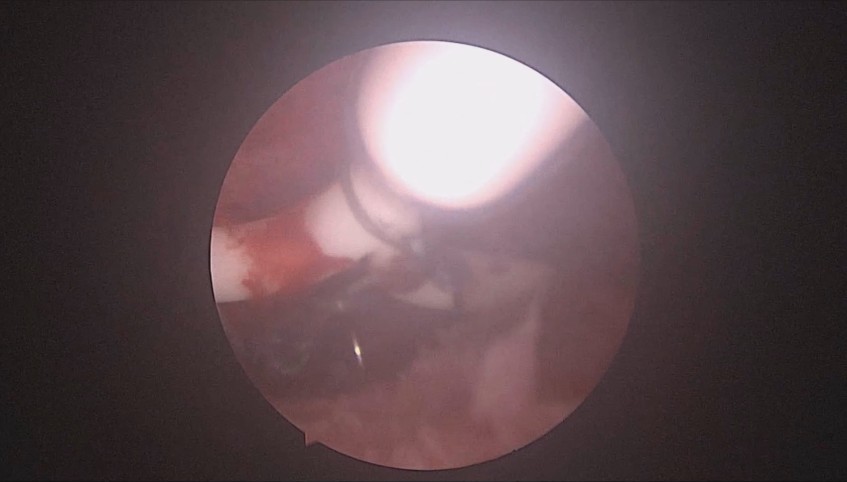

患者37岁,G3P1,剖宫产1次。子宫腺肌症合并子宫肌瘤6年,月经量增多1年。B超子宫前位,6.6cm*5.5cm*5.8cm大小,子宫后壁肌瘤直径6cm。2024年12月宫腔镜探查,宫深9cm,放置曼月乐并固定。用曼月乐尾丝在环横臂中间套扎形成线圈,异物钳夹持线圈挂到不锈钢挂钩里,将环固定于宫底,患者及家属拒绝内膜送病检。术后多次复查B超,曼月乐位置正常,最后一次环顶端距宫底1.2cm。